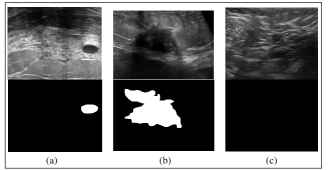

1.3.1 Dataset

Breast Cancer Dataset images are challenging to analyze due to low image quality, noise, and varying viewpoints due to the handheld nature of the sensor.

3.1 Dataset

The data examines ultrasound scans used to diagnose breast cancer. Pictures from the Breast Ultrasound Dataset are divided into normal, benign, and malignant images. Breast ultrasound pictures can yield excellent results for categorising, detecting, and segmenting breast cancer when used in conjunction with machine learning. Women between the ages of 25 and 75 are represented by breast ultrasound pictures in the baseline data. These numbers were gathered in 2018. 600 female patients make up the total number of patients. With an average image size of 500*500 pixels, the collection comprises of 780 images. PNG format is used for the pictures. The original photos are displayed alongside the real-world photographs. Three classes—normal, benign, and malignant—are established for the photos.